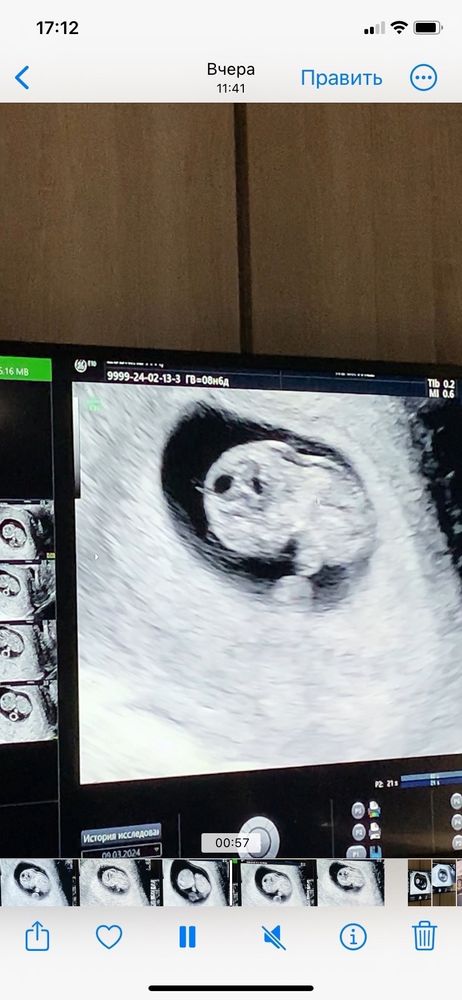

Узи 9 недель

Не паникуйте. Не понимаю врача, которая Вас напугала на таком сроке. ТВП измеряется ТОЛЬКО сроке 12 недель, т.е. на первом скрининга. Также ТВП смотрят вместе с КТР, если уже ТВП больше 3 будет на скрининге, тогда уже стоит дальше обследоваться и искать причину. Сейчас Вам просто бессмысленно измерили ТВП и напугали, успокойтесь и ждите скрининга. Хорошей беременности🌸

А какое твп?

Юлия, в том то и беда, что она его не измерила, сказала, что сейчас измерять будет нечестно и некорректно вроде бы. Я ей тем же вечером написала в социальной сети, она также ответила мне, хотя я просто спросила увеличено оно или нет